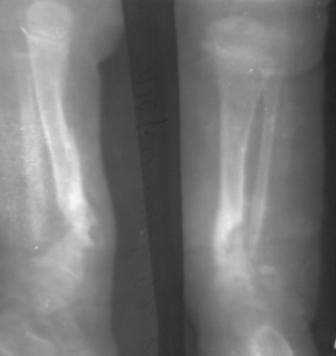

Ребенок август 2007г.р. В марте 2008г оперирован детским ортопедом, приглашенным из центра, клиновидная остеотомия, коррекция деформации, фиксация и/м спицами.

Через год рецидив деформации и л/с.

Родители родственники, родился 5 кг, по счету третий, ребенок упитанный (как говорят педиатры - лимфатик), левая нога укорочена на 2,5см. функция коленного и г/с суставов сохранена.

Наш план. 1-этап. аппарат Илизарова, коррекция деформации.

2-этап. Открыто освежение (по возможности до появления росы) и адаптация концов- образуется дефект, кортикотомия проксимального метафиза и удлинение по методу Илизарова, и фиксация на аппарате до консолидации.